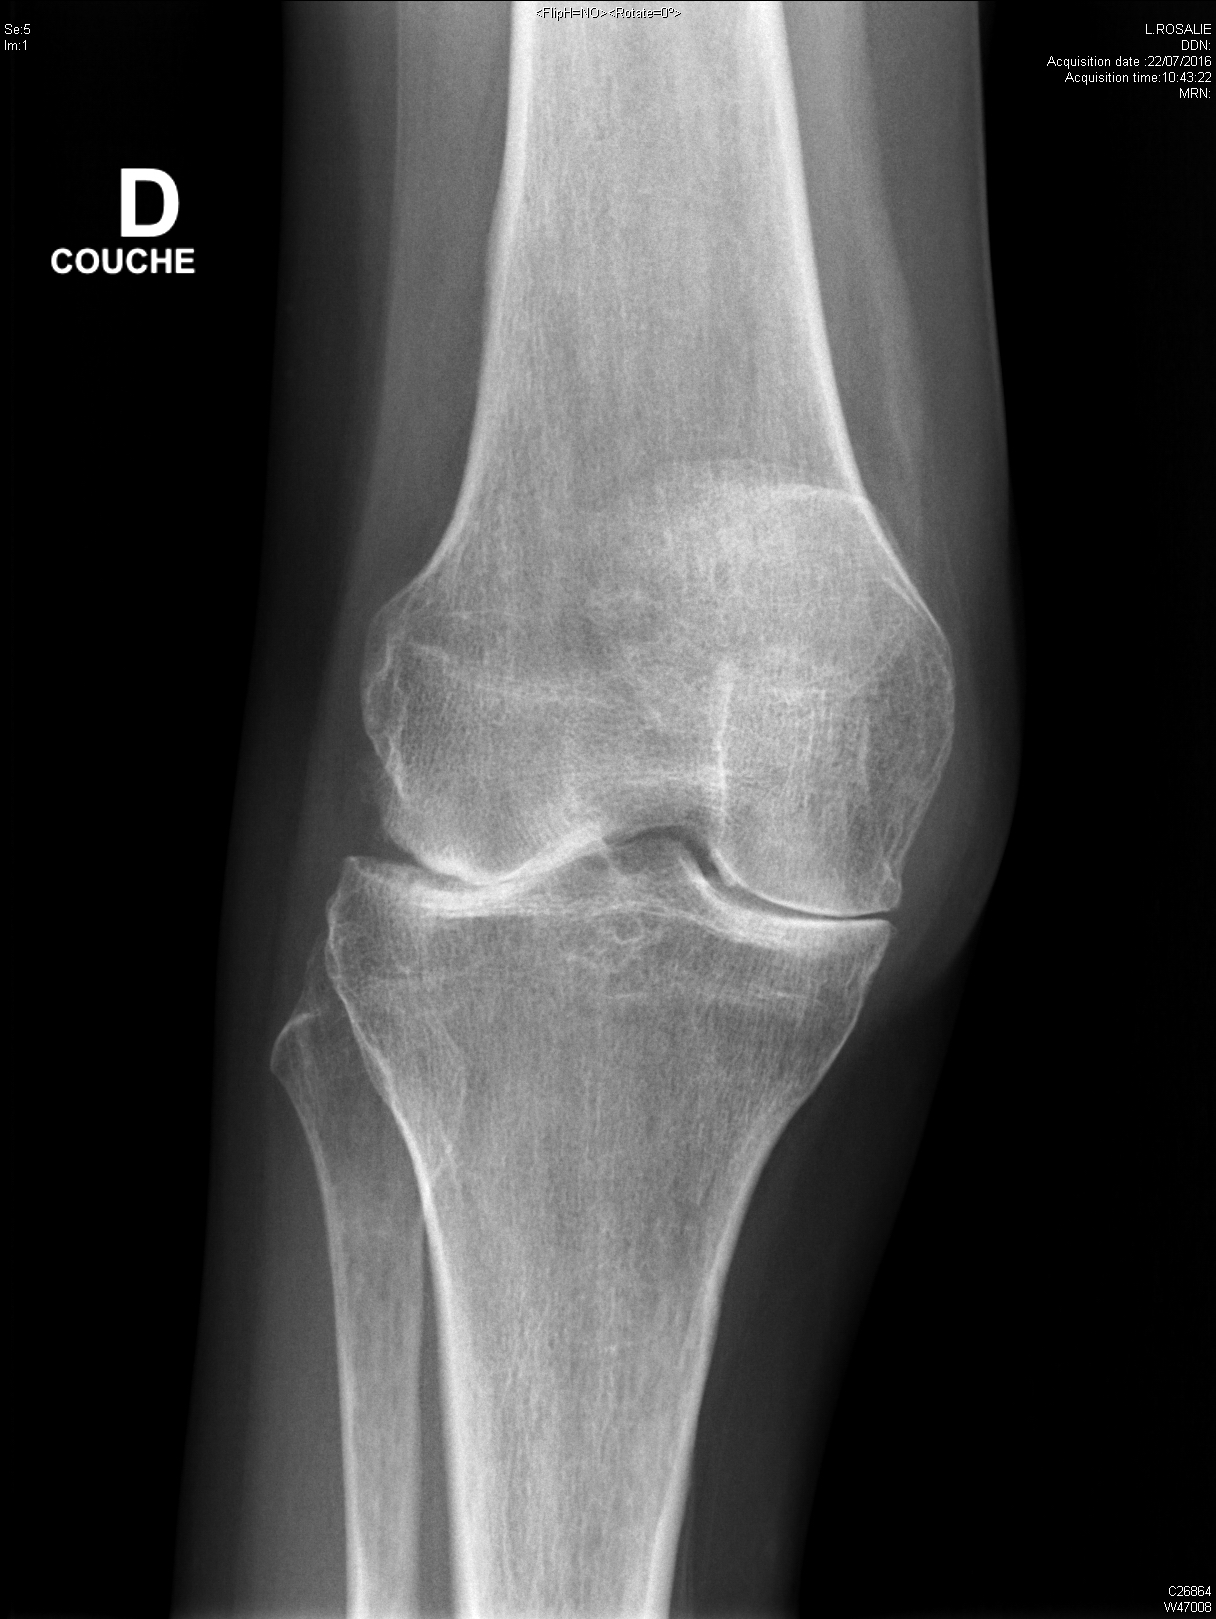

arthrite destructrice évoluée du genou dans le cadre d'une polyarthrite rhumatoïde

Gonarthrose évoluée sur terrain d'obésité